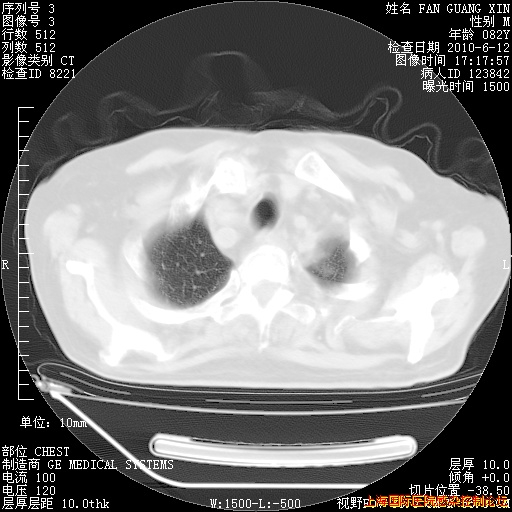

6月12日肺窗

6月12日纵膈窗